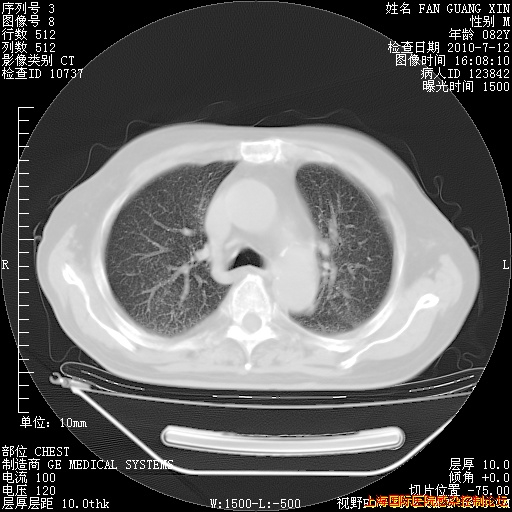

今天复查CT